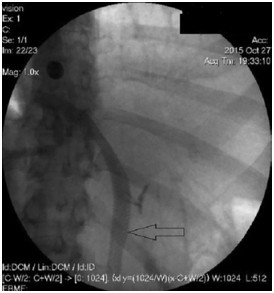

Abstract: Hilar cholangiocellular carcinoma (CCC) is a malignant neoplasm of epithelial origin occurring at the confluence of the right and left hepatic bile ducts. Typically, these tumors are small, poorly differentiated, exhibit aggressive biologic behavior with non-specific symptoms and tend to obstruct the intrahepatic bile ducts. Surgery is the only available curative option. Unfortunately, in less than half of the patients a complete resection is possible with poor survival rate in unresectable cases. In this report, we present the case of a 58-year-old woman with a history of unresectable hilar cholangiocarcinoma. Initially she was treated with intraductal dilatation of malignancy and placement of a plastic stent and chemotherapy (Gemcitabin® and Platinol®). Two years later she underwent a second-line chemotherapy with Gemcitabin® and Oxyplatin® because of tumor progression. Despite a second line chemotherapy and placement of an uncovered self-expandible metal stent (ucSEMS) that was extended later on by stent-in stent technique, there was tumor progression which led to a complex course with relapsing obstructive cholangiosepsis and cholestasis. Because of tumor ingrowth, endobiliary radiofrequency ablation of the malignant stenosis was performed in repeated sessions. This case illustrates that radiofrequency ablation of solitary malignant biliary obstruction is feasible, safe and allows an improvement of quality of life in non-operable patients.